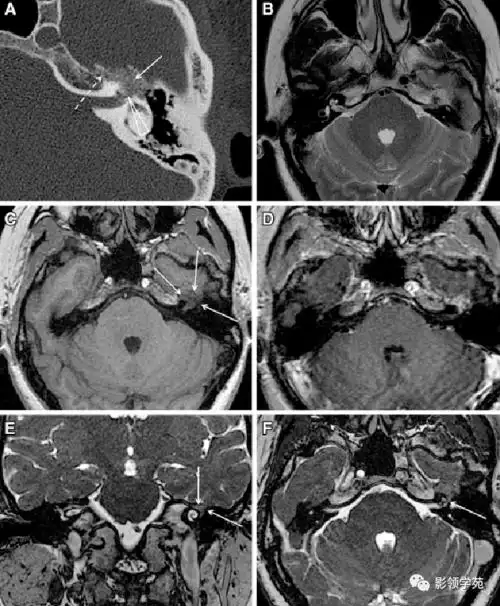

面神经解剖与常见疾病

面神经解剖及相关病变